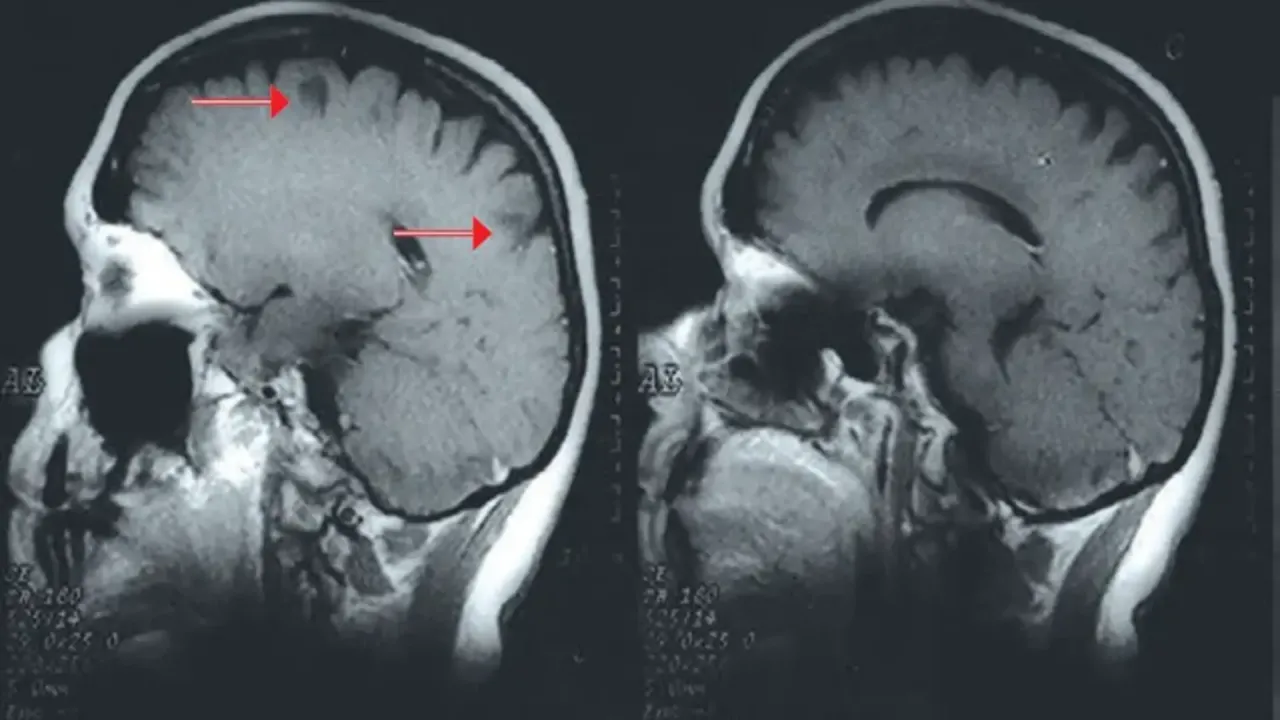

Drugi akt to aura migrenowa, doświadczana przez około 25% chorych. Jest to fascynujący, choć często przerażający, zespół odwracalnych objawów neurologicznych, które zazwyczaj trwają od kilku do 60 minut i poprzedzają ból głowy. Najczęściej spotykamy się z objawami wzrokowymi: migającymi światłami, zygzakowatymi liniami (nazywanymi czasem "widmami fortyfikacyjnymi"), mroczkami czy ubytkami w polu widzenia. Niektórzy opisują to jako patrzenie przez rozbite szkło. Mogą również wystąpić objawy czuciowe, takie jak mrowienie lub drętwienie palców, dłoni, ramion, a nawet twarzy czy języka. Rzadziej pojawiają się przejściowe zaburzenia mowy, które mogą być bardzo niepokojące.

Zaburzenia wzrokowe: Mroczki, błyski i zygzaki, które maluje mózg

Najczęstszymi i najbardziej rozpoznawalnymi objawami aury są zaburzenia wzrokowe. Pacjenci często opisują je jako mroczki (ubytki w polu widzenia, które mogą się powiększać), migające światła, błyski lub charakterystyczne, zygzakowate linie, które powoli rozprzestrzeniają się w polu widzenia. Te "widma fortyfikacyjne" mogą tworzyć skomplikowane wzory, przypominające mury zamkowe. Czasem pojawiają się również zniekształcenia obrazu, takie jak falowanie, powiększanie lub pomniejszanie przedmiotów. To wszystko dzieje się, zanim pojawi się ból, co jest dowodem na złożone procesy neurologiczne leżące u podstaw migreny.